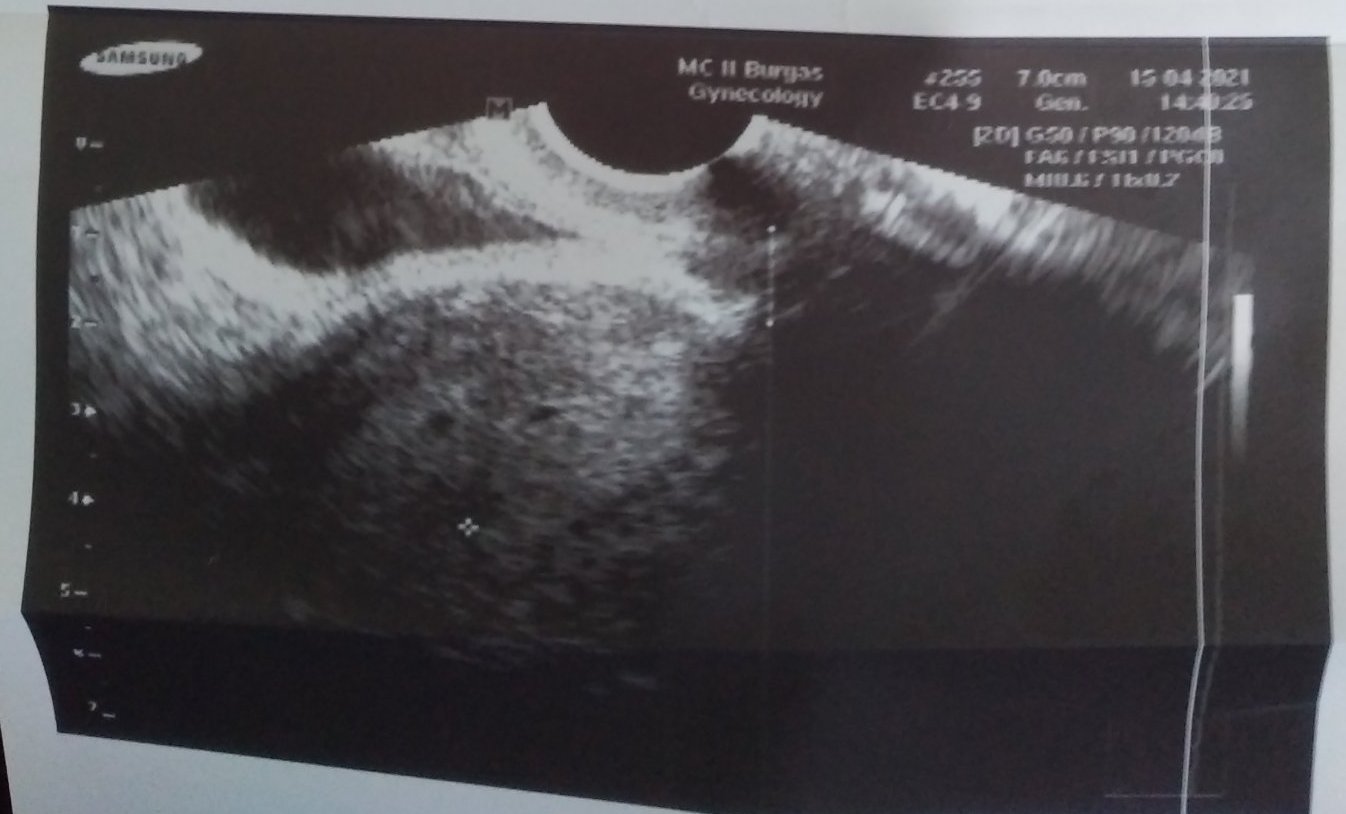

Може ли да попитам на тая снимка дали са близнаци доктора каза че не е сигорно

Може и сянка да е